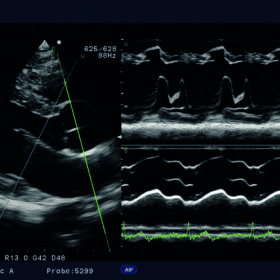

The Free Angular M-mode (FAM*) can be implemented in real time or reconstructed from the cine memory. Orientation at arbitrary angles allows for variation position. Whereas blood flow mapping with eFLOW allows demonstration of vascularity with high spatial resolution and minimal blooming.

High Frame Rate Zoom enables enlargement of a region of interest while maintaining a high frame rate on Hitachi Aloka F37. The Dynamic Slow-motion Display (DSD) offers detailed observation of fast moving structures such as the heart valves demonstrated with the real-time image alongside a slow motion counterpart.

| Καρδιακές λειτουργίες | ECG module, FAM (Free Angular M-mode), Tissue Doppler Imaging (TDI) |

Aloka UST-5299 Cardiac Phased Array